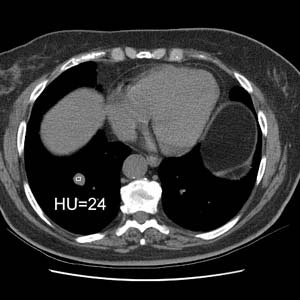

The patient was a middle aged female who had a slowly enlarging mass in the right lower lung. The patient was reluctant to have surgery, but contrast enhanced CT revealed nodule enhancement greater than 20 HU which suggested a malignant lesion and the patient agreed to surgery. The lesion proved to be a carcinoid tumor with atypical features at histologic analysis. Peripheral carcinoids are more frequently atypical as in this case.CXR revealed a right lower lobe non-calcified mass (yellow arrow):

The lesion enhanced 52 HU after IV contrast administration which suggested a malignant lesion- it was removed and found to be an atypical carcinoid: